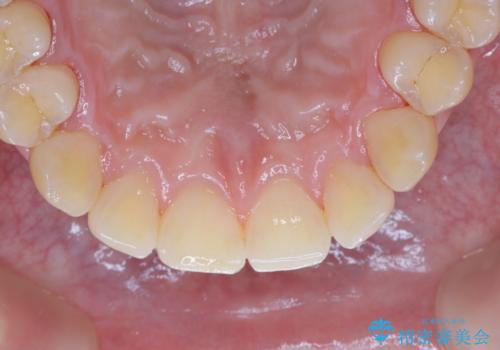

数年ぶりに歯のクリーニング(PMTC)

- しばらく歯科へ行っていなかったため綺麗にクリーニングしたいとのことでした。全体的に汚れが付着していたためPMTC60分コースを行いました。